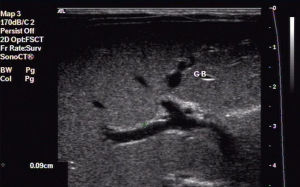

2.B超檢查

最為簡便且無創的檢查手段,可初步獲得診斷。肝臟下方顯示界限清楚的低回聲區,並可查明肝內膽管擴張的程度和範圍及是否合併膽管內結石。